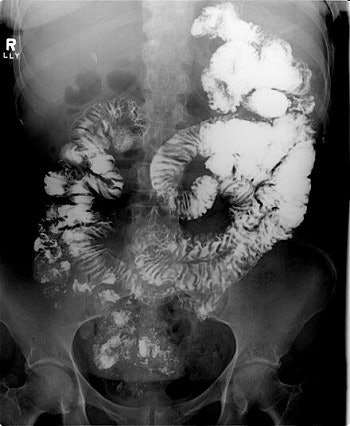

Both UGI and CT detect signs signaling adhesion or internal hernia, such as dilated bowel segments and a transition from dilated to collapsed bowel. But only CT depicts classic signs of internal hernia such as crowding, stretching, and engorgement of mesenteric vessels.

Three images show internal hernia following Roux-en-Y gastric bypass. The CT scans (top, middle) and small bowel study (below) show a cluster of mildly dilated bowel segments in the left abdomen, with a crowded, twisted appearance of the bowel and mesenteric vessels. Images courtesy of Dr. Michael Federle.